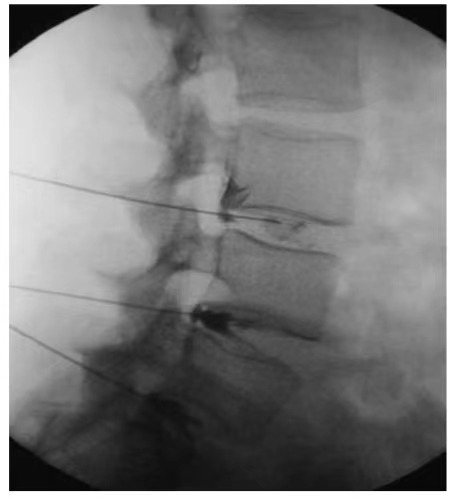

Наша команда специалистов разработала технологию CT-направленных интраспинальных инъекций, специально предназначенную для терапии стволовыми клетками при лечении травм спинного мозга. Во время процедуры визуализация в реальном времени с помощью КТ создаёт динамическое 3D-изображение позвоночника, позволяя хирургам вращать и анализировать локализацию переломов в многомерном пространстве. Игла аккуратно продвигается по здоровому анатомическому пути, избегая костных препятствий. По мере того как хирург направляет иглу к спинному мозгу, система постоянно обновляет изображение, проверяя углы траектории и пространственные соотношения между спинным мозгом и позвонками, обеспечивая абсолютную точность и безопасность. Эта техника часто комбинируется с люмбальными пункциями или внутривенным введением стволовых клеток для повышения эффективности.

Преимущества CT-направленной инъекции в позвоночник:

1. Минимально инвазивная и безопасная

Без крупных разрезов. Проводится под местной анестезией с минимальной травматичностью, кровопотерей и послеоперационной болью, что обеспечивает быструю реабилитацию.

2. Субмиллиметровая точность

CT-навигация позволяет в реальном времени измерять и точно направлять иглу к месту поражения с непревзойдённой точностью.

CT-направленная инъекция в позвоночник предлагает революционное, безопасное и эффективное решение для пациентов с травмой спинного мозга, значительно улучшая клинические исходы и качество жизни. Если вы или ваш близкий сталкиваетесь с травмой спинного мозга, обратитесь к нашей специализированной медицинской команде сегодня. Вместе мы разработаем индивидуальный план лечения, чтобы возродить надежду и помочь вам вернуть независимость.